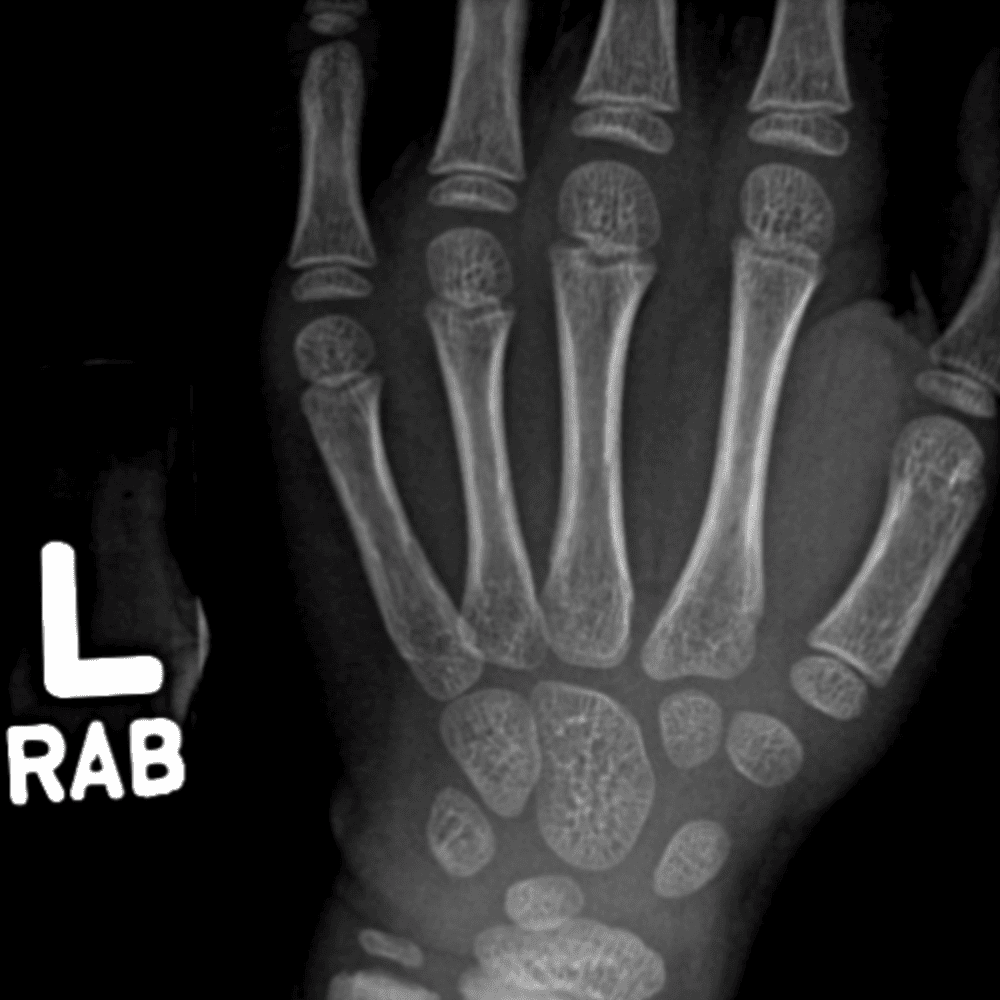

Simulates call by including subtle or difficult cases and some normals.

30 cases